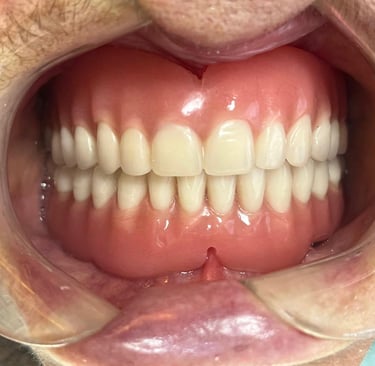

Aspecto Clínico Final - Fotografias originais — nenhuma contém retoques — A cor dos dentes é escolhida de acordo com o gosto e a preferência estética de cada paciente.

Prótese total convencional

Depois

Solução tradicional e econômica para quem perdeu todos os dentes. Embora a prótese protocolo sobre implantes ofereça mais estabilidade, a prótese total continua sendo uma alternativa acessível que devolve função e estética ao sorriso.